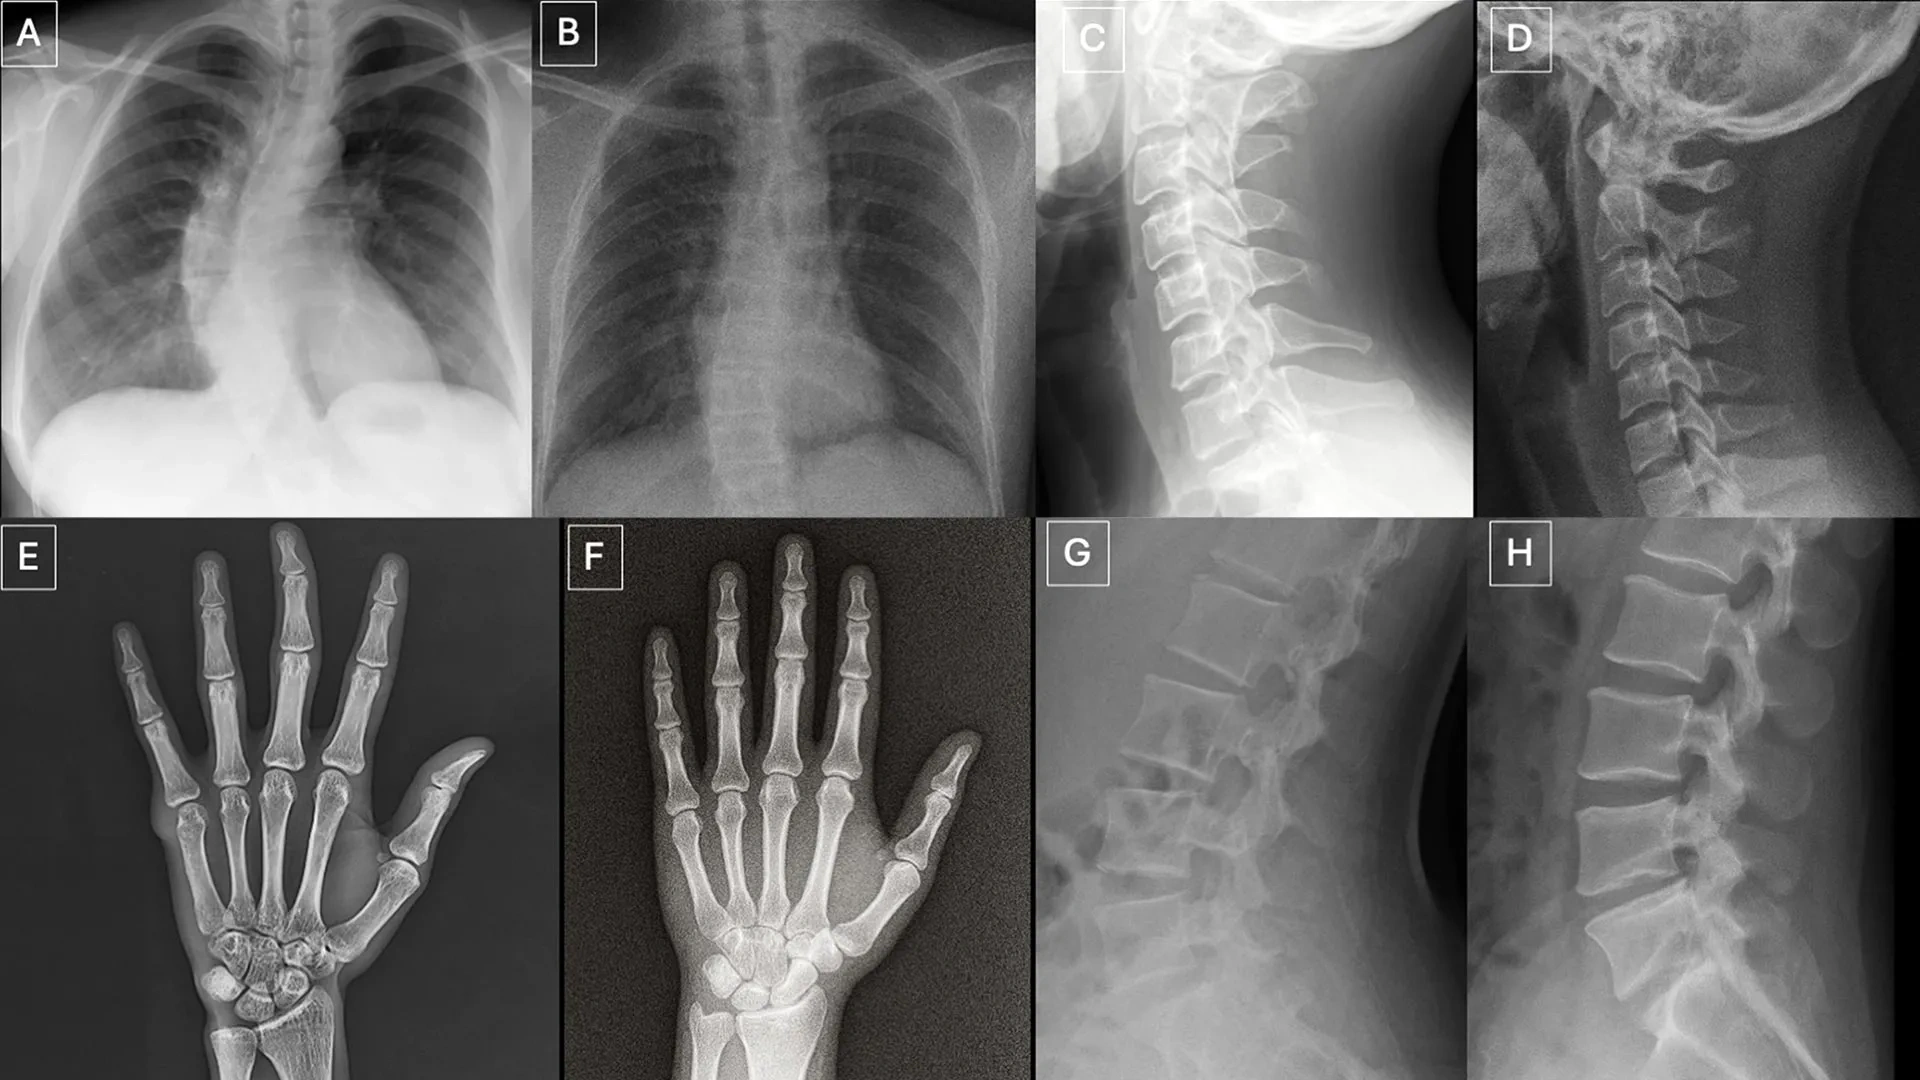

图源:The Rise of Deepfake Medical Imaging:Radiologists’ Diagnostic Accuracy in Detecting ChatGPT-generated Radiographs

图源:The Rise of Deepfake Medical Imaging: Radiologists’ Diagnostic Accuracy in Detecting ChatGPT-generated Radiographs

该项研究由纽约西奈山伊坎医学院研究团队完成,共纳入了来自6个国家的12家机构的17名放射科医生,涵盖了从初学者到执业40年的资深专家。研究共测试了264张X光片,其中包括由ChatGPT生成的身体各部位影像,以及使用斯坦福大学开发的开源生成式AI扩散模型RoentGen生成的胸部影像。

研究人员指出,这些高度逼真的伪造影像不仅可能在虚假诉讼中作为证据,还存在严重的信息安全风险。若黑客侵入医院网络并注入合成影像,可能导致误诊并破坏数字病历的可靠性。目前,伪造影像在视觉上呈现出“过于完美”的特征,如骨骼过滑、脊柱异常笔直、血管分布过度均匀等,但在未来的AI演进中,这些特征可能进一步消失。